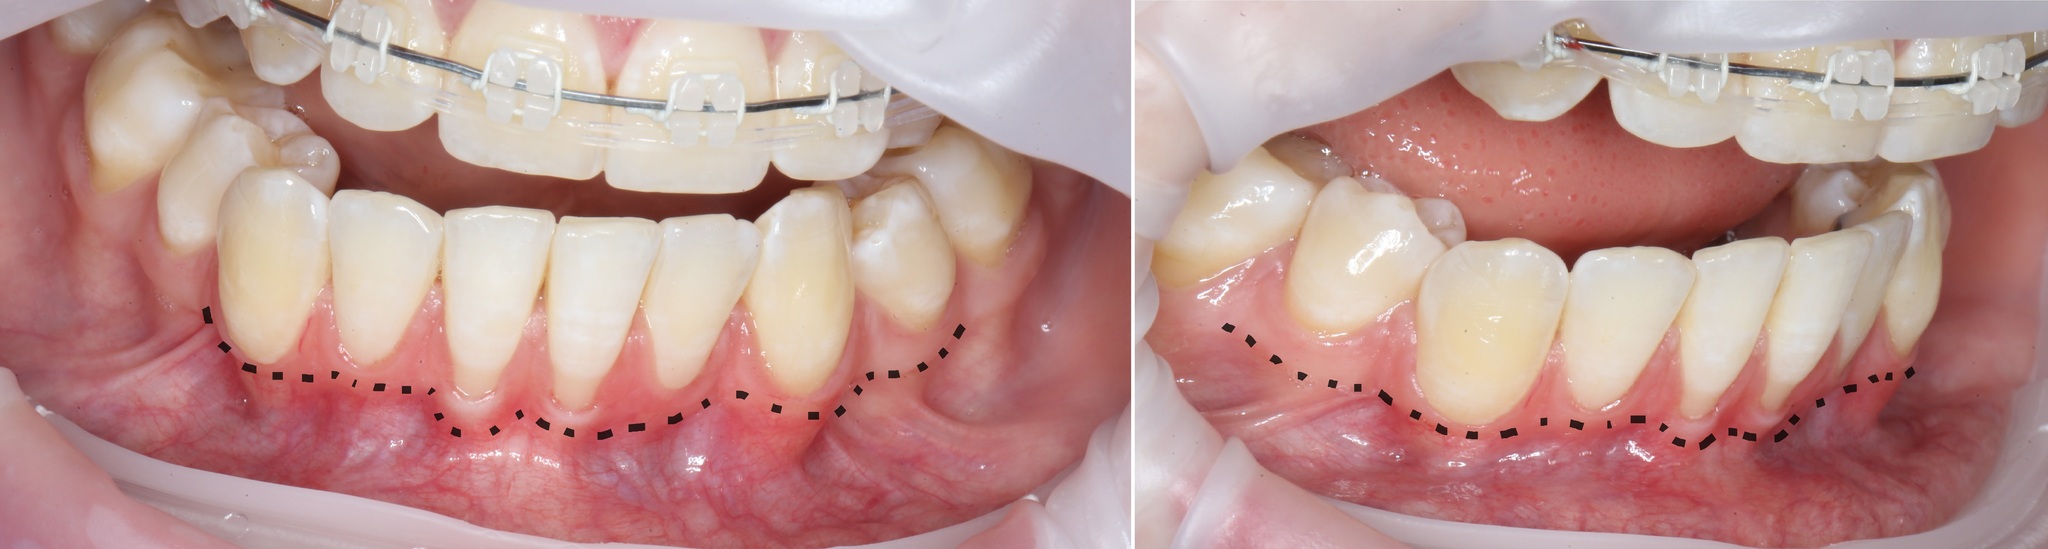

Фотографии, сделанные на первичной консультации:

Ниже пунктиром отмечен переход подвижной слизистой в неподвижную. В некоторых местах, особенно в области центральных резцов прикрепленной десны, практически нет. В связи с чем образовались такие явные рецессии. Видно?